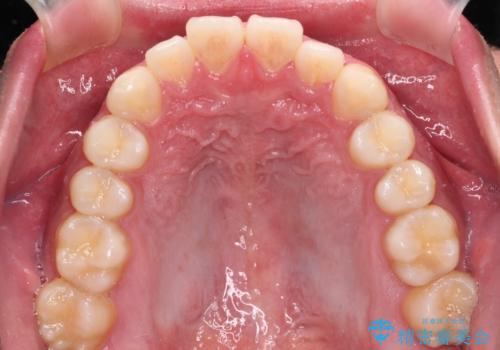

- 20代男性

- インビザライン・ライト

- 8ヶ月

- 上下前歯の叢生を気にして来院された患者様です。

費用を抑え、期間もあまりかけずに治療をしたいとのことで、インビザライン・ライトを用いて矯正治療を行うこととしました。